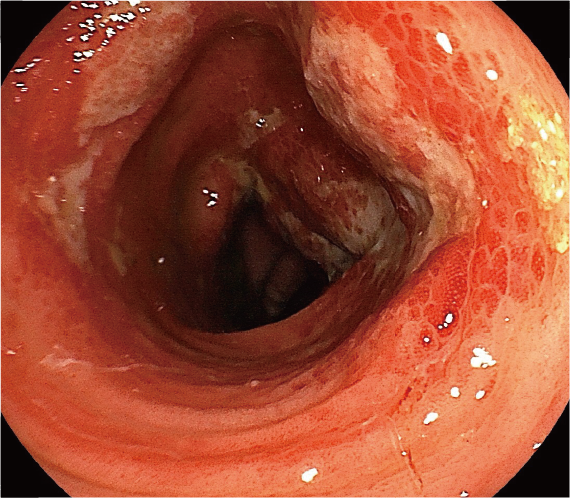

10日前から下痢、血便を認める患者さんの診断名は?

- 出血源の検索を目的に、大腸内視鏡検査および生検組織学的検査を施行した。

●大腸内視鏡検査